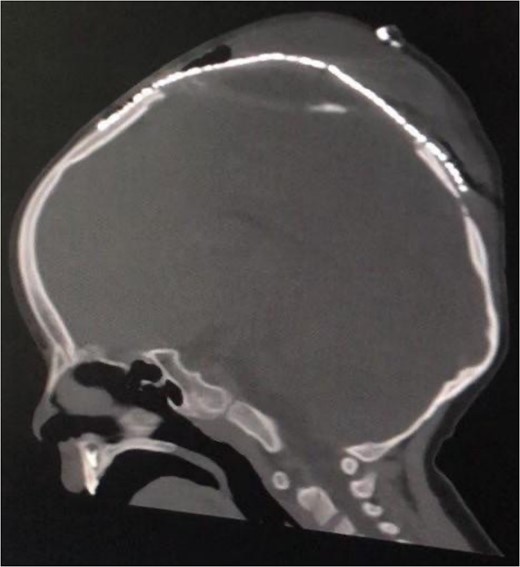

Furthermore, a decision to perform a cranioplasty was made immediately. In the operation the previous bicoronal flap was reopened, isolating the encephalocele. It was found a newly formed tough ring of bone encircling the base of the encephalocele, with the edges of this bone intruding into the brain tissue with significant adhesions, indicating abnormal bone growth around the affected area. Carefully, the newly formed bone was removed to reach the healthy bone of the skull. A temporary EVD was used alongside mannitol administration and hyperventilation to reduce the CSF. The sac was pushed inside and subsequently, a decision for 3D cranial mesh (Fig. 3) closure was made to cover the defect in the cranium for finally close the incision normally. Postoperative CT scan was done (Fig. 4), demonstrating that the brain went inside with no postoperative complications. There was notable improvement in the motor functions of the right limbs and absence of spasticity in the right upper limb. Two days later the patient was discharged home, active and able to walk without assistance.

Postoperative sagittal brain CT demonstrating that the brain was inside the cranium and covered by the cranial mesh, preventing further bulging.